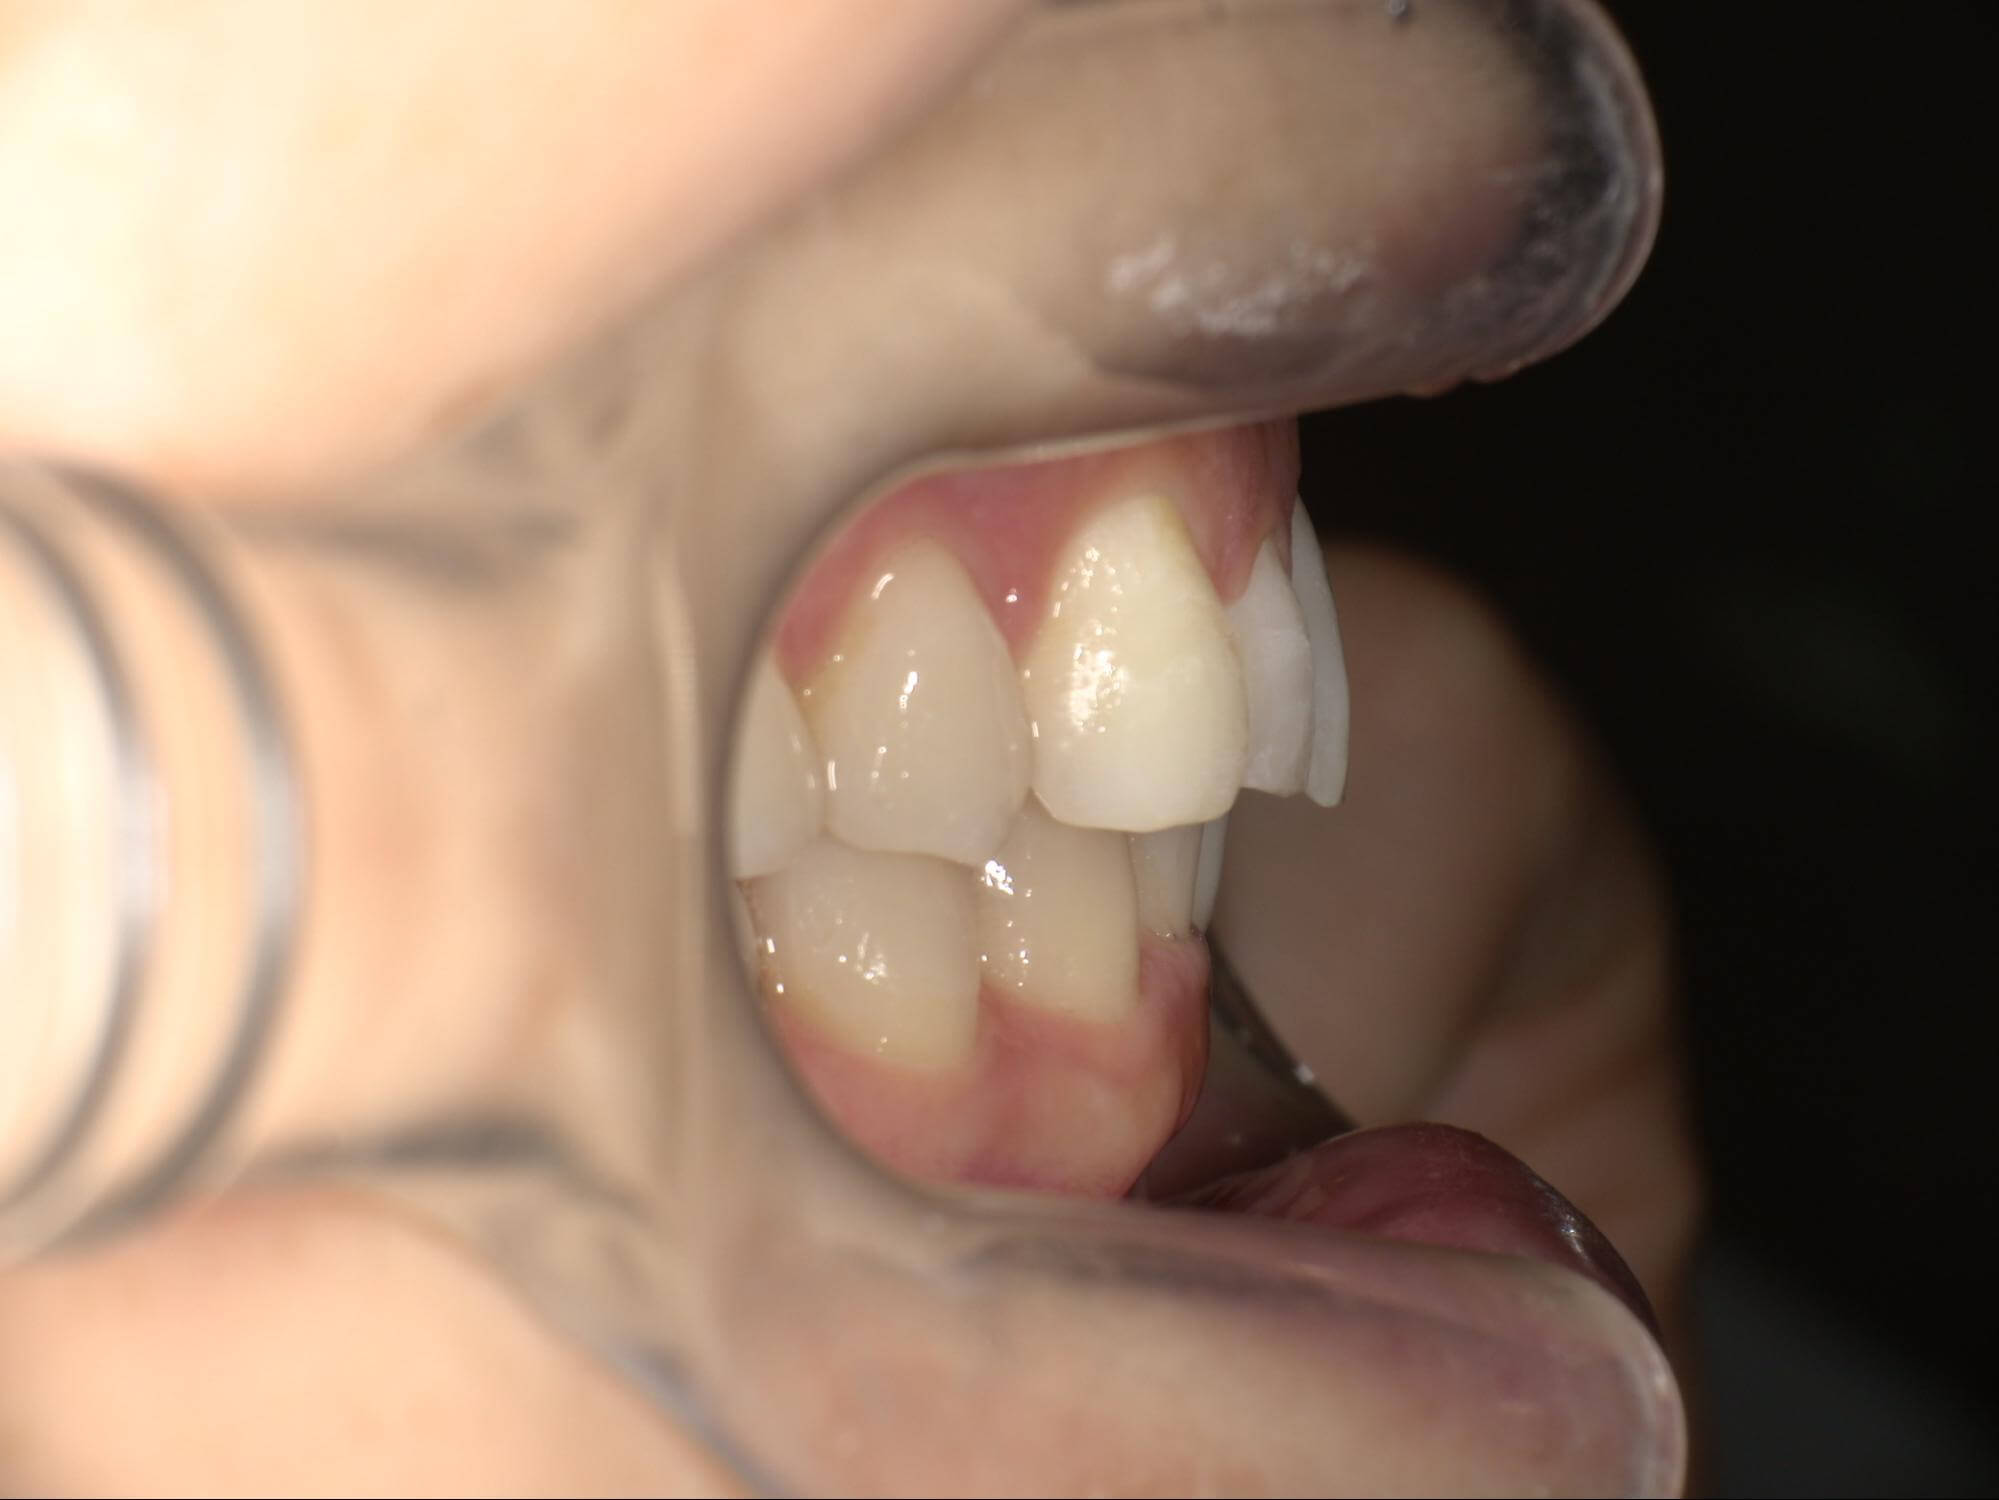

| 年齢・性別 | 21歳 |

|---|---|

| 主訴 | 叢生が気になる・前歯に埋伏歯がある |

| 治療期間・回数 | 6ヶ月 |

| 費用 | 935,000円 |

| 上顎の左側3番が埋伏していたため、上顎左右の3番および親知らずを抜歯し、矯正治療を行いました。 治療開始からおよそ6ヶ月で歯列が整い、審美的にも機能的にも良好な結果が得られた症例です。 |